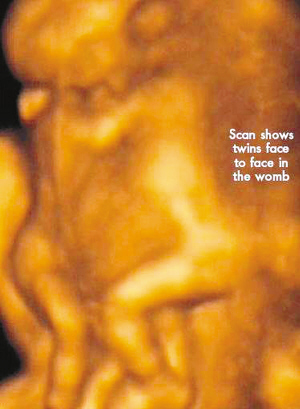

麗莎每周都要到醫院接受醫學掃描,而她腹中的連體嬰也讓醫生感到驚訝不已,因為他們已經打破了醫生的死亡預言,一直在母親子宮中堅強活到了現在。麗莎將于兩周內接受剖腹產手術。